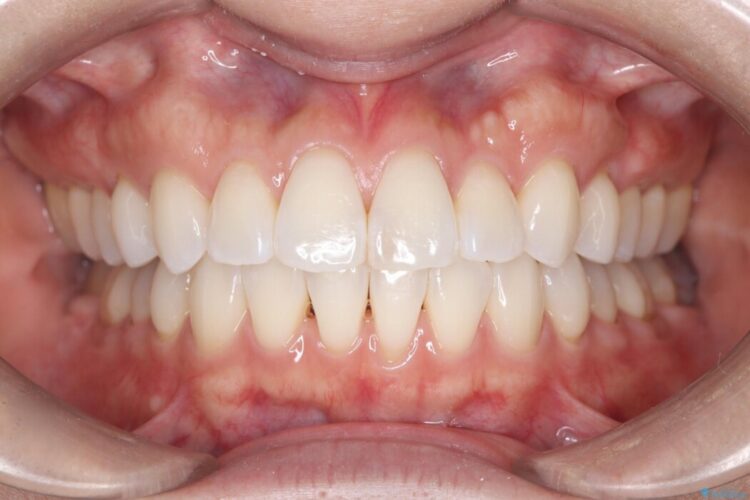

まずはこの装置で奥歯の土台を安定させつつ、ワイヤー装置による繊細な歯の移動を組み合わせることで、非抜歯で歯列全体のアーチを整えていきました。シザーズバイトが解消されたことで、奥歯でしっかりと物を噛めるようになり、顎の動きもスムーズに改善されました。

治療完了後、前歯のガタつきはきれいに整い、上下の奥歯も理想的な位置で噛み合うようになりました。非抜歯での治療により、ご自身の歯をすべて残したまま、機能的で美しい歯並びを実現することができました。